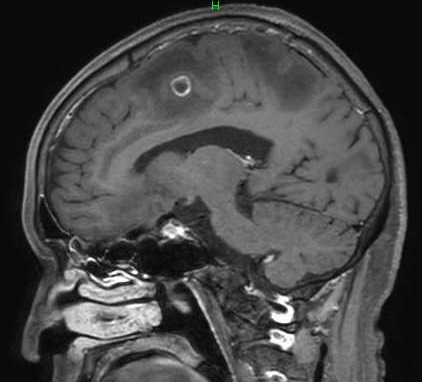

MRI検査

MR検査はがん診療において、CT検査と比較してより詳細な検査が可能です。

各臓器において浸潤範囲を描出することができ、治療範囲の決定のための広がり診断をすることができます。MRI検査は検査時間が長く、撮像できる範囲に制限があります。

MRI検査では造影剤が使用されます。

乳房造影MRI検査画像